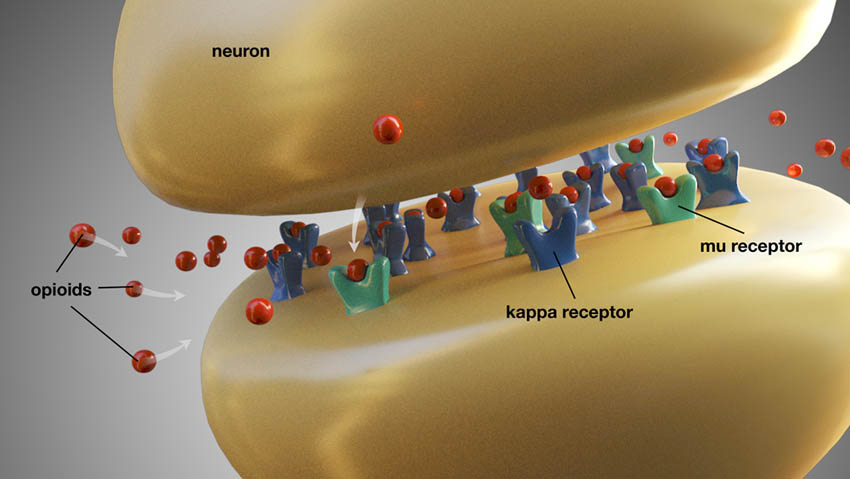

Τα οπιοειδή που συνταγογραφούνται συνήθως για τον οδοντικό πόνο περιλαμβάνουν την κωδεΐνη, την υδροκωδόνη, την οξυκωδόνη και την τραμαδόλη. Αυτά τα φάρμακα μπορούν να συνταγογραφηθούν από μόνα τους ή σε συνδυασμό με ακεταμινοφαίνη. Τα οπιοειδή ασκούν τη δράση τους αλληλεπιδρώντας με τους μ- και κ-υποδοχείς στο κεντρικό νευρικό σύστημα και αλλοιώνουν την αντίληψη του πόνου (Εικ. 5). Μπορούν να δημιουργήσουν μία αίσθηση ευφορίας και να μειώσουν το άγχος. Έτσι, ακόμη και εάν είναι πιθανόν να μην προσφέρουν πλήρη ανακούφιση από τον πόνο, ενδεχομένως να κάνουν τους ασθενείς να ασχολούνται λιγότερο με τον πόνο που νιώθουν. Τα οπιοειδή συνοδεύονται από μία πληθώρα παρενεργειών, στις οποίες συμπεριλαμβάνονται η ναυτία, ο έμετος, η δυσκοιλιότητα, τα ψυχοκινητικά προβλήματα και η καταστολή του ΚΝΣ.

νευρώνας

οπιοειδή

κ-υποδοχέας

μ-υποδοχέας